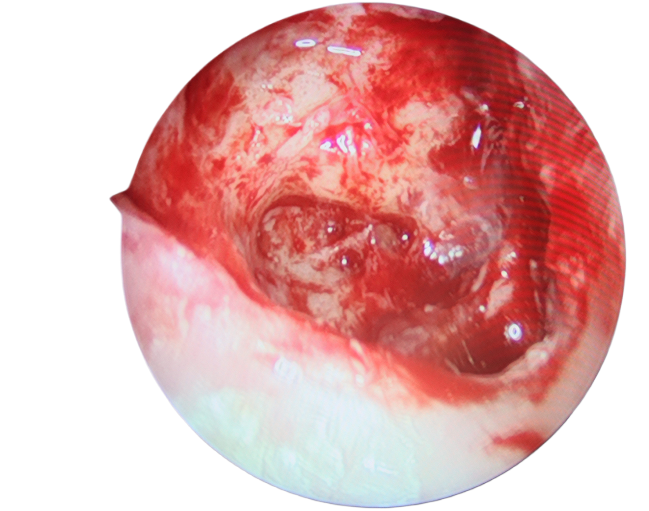

手術(shù)中,使用微動力系統(tǒng)及耳電鉆磨開乳突骨質(zhì),在乳突氣房中發(fā)現(xiàn)大量膿性分泌物,取以刮匙清理干凈。隨后,又在顱內(nèi)硬腦膜外發(fā)現(xiàn)大量膽脂瘤型分泌物,遂予徹底清除。